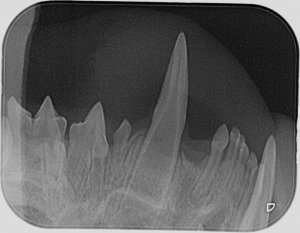

Ich hab zwar hier schon einige röntgenzahnbilder gesehen wo von Knochenabbau die rede war, deswegen hatte ich die Stellen markiert wo es (für mich ) auch so aussah, aber wahrscheinlich ist das in Ordnung so. Ich hoffe ja dass sich dazu noch jemand meldet und mir grünes Licht gibt.